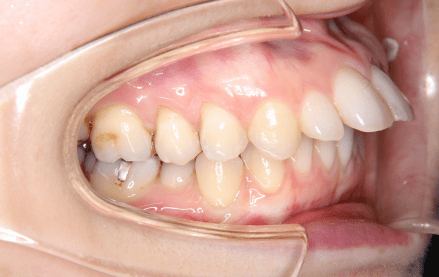

上顎前突は、いわゆる出っ歯の状態で奥歯をかみ合わせた状態で、上下の前歯が離れて前後的な隙間がある状態のことを指します。

上顎前突の原因としては、かみ合わせた際の上下の顎の骨の位置にずれがある場合(①骨格性)や、上下の前歯の生えている方向が悪い場合(②歯性)、また幼少期の指しゃぶり原因であることもあります。